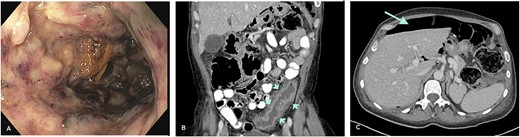

A sigmoidoscopy revealed severe inflammation with deep ulcers and patches of mucosal necrosis (Fig. 1A). Biopsies from the rectum and distal colon showed severe inflammation and necrosis, and immunohistochemistry (IHC) for CMV was negative. Treatment was changed to intravenous methylprednisolone 50 mg/day and metronidazole/ciprofloxacin. An abdominal computed tomography (CT) scan revealed a left-sided colonic wall thickening with free intra-abdominal air (Fig. 1B and C). Emergency laparoscopy showed purulent peritonitis with a perforation of the descending colon. Due to the lack of inflammation of the right colon and according to the patient’s preference to avoid subtotal colectomy, a laparoscopic left hemicolectomy with formation of an end colostomy (Hartmann’s procedure) was performed. Postoperatively, the patient’s condition improved rapidly. Biologic therapy with infliximab was started 2 days after surgery to address the severe proctitis and potential inflammation in the remnant colon. Gross specimen examination showed a severe diffuse necrotizing colitis, and histology revealed an extensive ulcerating colitis with pseudomembranous character with patchy, transmural necrosis and perforation in the proximal descending colon (Fig. 2A, B1 and C1). The mucosal inflammation ended abruptly adjacent to the perforation, and the oral resection margin showed normal mucosa, whereas the aboral margin was heavily inflamed and partially necrotic.

(A) Severe colitis with deep ulcerations on endoscopy. (B) Left-sided colonic wall thickening (CT-scan; short arrows). (C) Intraperitoneal air indicative of hollow viscus perforation (CT-scan; long arrow).